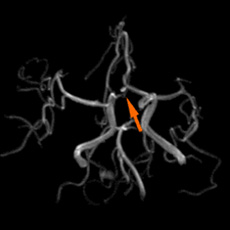

• 頸部MRA2mm大の脳動脈瘤

2mm大の脳動脈瘤